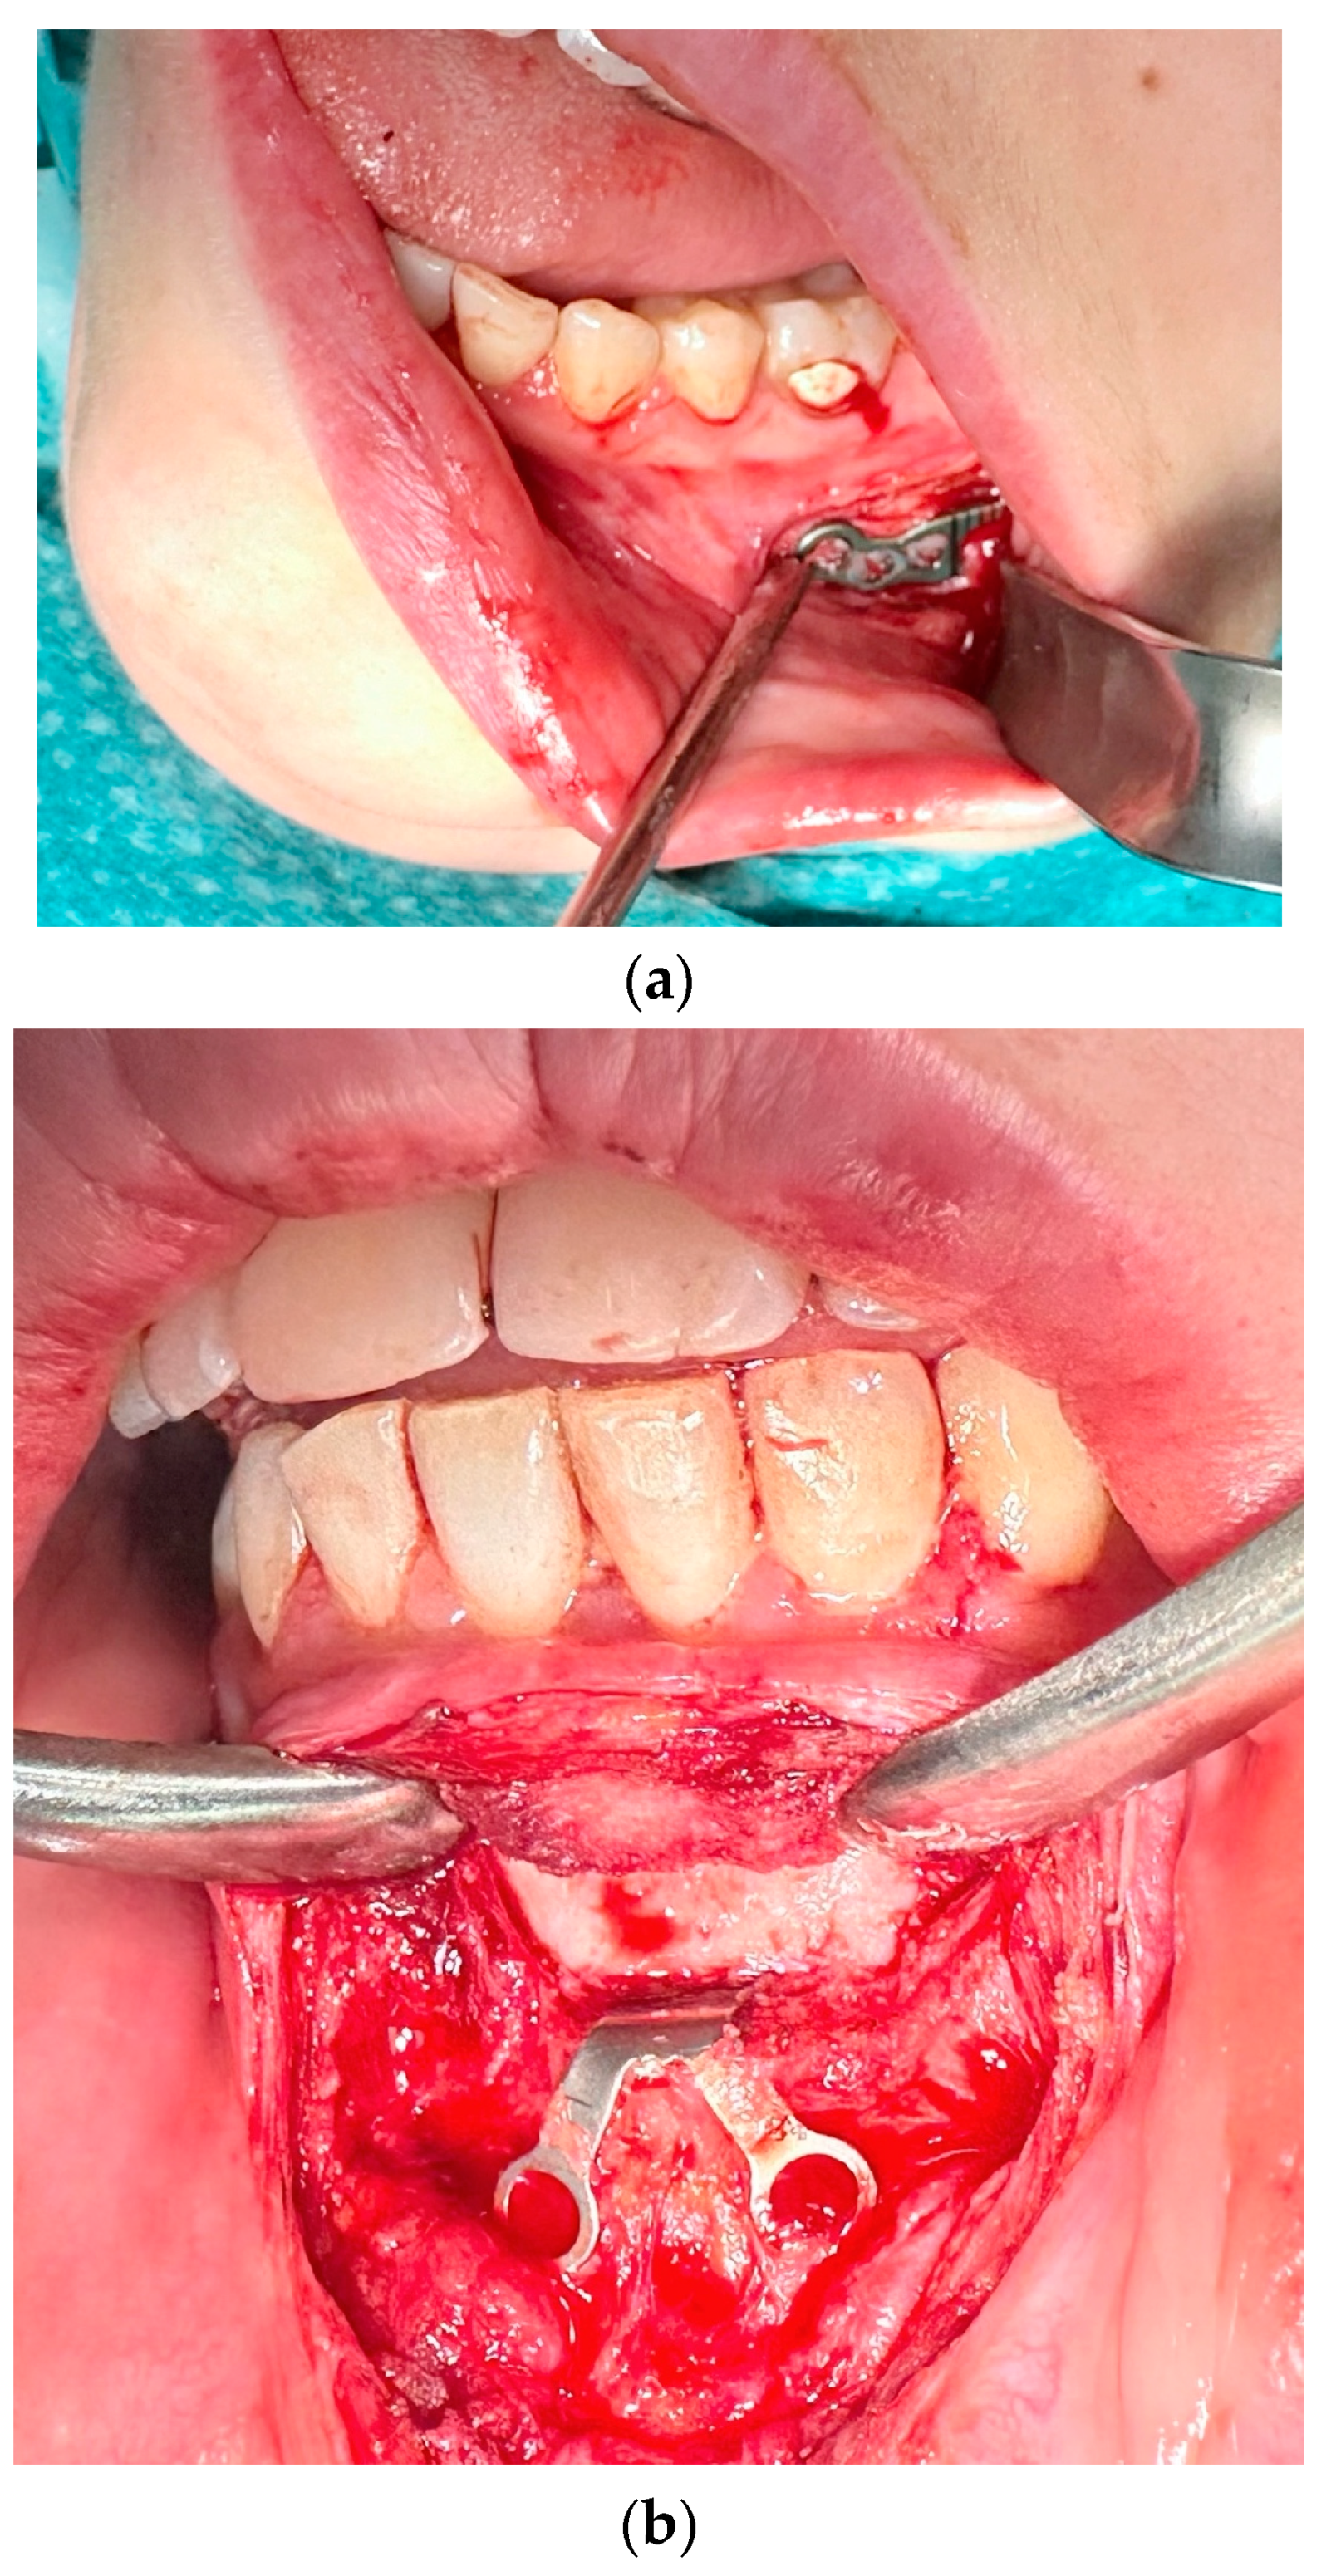

The first group included complications such as the occurrence of inflammation, infection, and fistula in the fixation area, swelling, or fixation exposure (Figure 2). This occurred in 17 cases, representing 22.08% of 77 fixation hardware removal procedures and 11.97% of 124 orthognathic procedures performed.

Figure 2.

Image of inflammation/infection: (a) intraoral photo with fistula in the fixation area; (b) CBCT mandibular screws not fixed due to inflammation; (c) CBCT osteonecrosis in the bicortical screw area.

In instances of inflammatory complications or infections, the affected area in 11 cases was the maxilla and in 6 cases it was the mandible.

In 4 of 17 cases where complications were the reason for osteosynthesis removal, only the hardware that caused the problem was removed, and in the remaining 13 cases, all fixation hardware was removed at the same time.